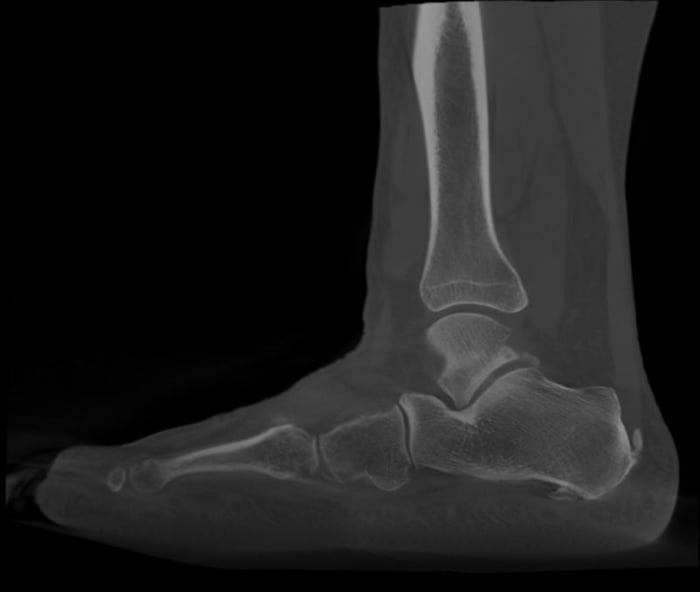

- Il problema è nel piede, che è cavo, oppure piatto.

- Per un piede cavo (più rigido):

- Una semplice talloniera antishock, con l'obiettivo di ridurre lo stress biomeccanico sotto al calcagno, può essere d'aiuto.

- In questi casi, l'appoggio a tripode del calcagno (calcagno, base del quinto e primo metatarsale) è accentuato, e ridurlo nell'area sofferente può portare beneficio. È consigliato un modello che occupi poco spazio nella scarpa.

- Per un piede piatto patologico:

- La talloniera non è sufficiente. In questo caso, alla soletta si chiederà di favorire la funzione del piede, messa a dura prova dal piattismo patologico.

- Il piede piatto patologico stressa la funzione di un tendine (il tibiale posteriore) e di legamenti adiacenti (deltoide nella caviglia e spring ligament nel piede) che tendono a cedere, esponendo la fascia plantare a un eccesso di fatica.